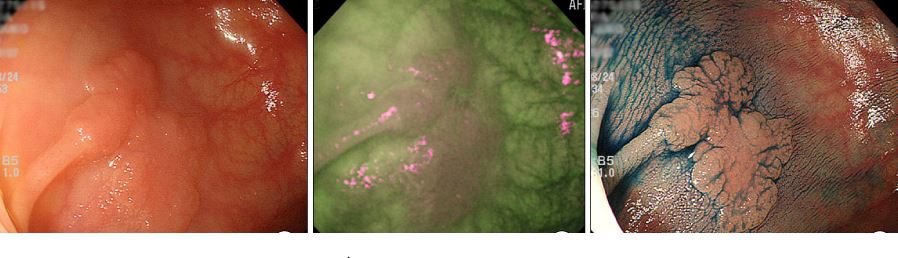

Επίπεδος πολύποδας α)χωρίς β)με ηλεκτρονική και γ)με συμβατική χρωμοενδοσκόπιση

Όπως ήδη έχουμε περιγράψει υπάρχουν διαφορετικές μορφές πολυπόδων στο παχύ έντερο. Οι συνηθισμένοι είναι αυτοί που προέχουν στην εσωτερική επιφάνεια του εντέρου σαν εξογκώματα ή άλλοι που σχεδόν μοιάζουν με ένα μανιτάρι. Μπορούν εύκολα να εντοπιστούν και να αφαιρεθούν άμεσα κατά την διάρκεια μιας κολονοσκόπησης. Ωστόσο υπάρχει και μια άλλη μορφή πολυπόδων που ονομάζονται επίπεδοι και εκτείνονται σχεδόν παράλληλα με την επιφάνεια του εντέρου. Οι επίπεδοι πολύποδες δεν είναι πάντα εύκολο να ανιχνευθούν στην κολονοσκόπηση, αφού δύσκολα διακρίνονται από την υπόλοιπη επιφάνεια του φυσιολογικού βλεννογόνου. Ευτυχώς, τα σύγχρονα ενδοσκόπια, που διαθέτουν υψηλή ανάλυση αλλά και δυνατότητα μεγέθυνσης της εικόνας αλλά και η συσσωρευμένη εμπειρία των ενδοσκόπων έχει λύσει το πρόβλημα αυτό. Επίσης, είναι δύσκολο να προσδιορισθεί το ακριβές μέγεθός τους. Για αυτό το λόγο υπάρχουν διάφορες τεχνικές με την βοήθεια των οποίων μπορεί κανείς να διακρίνει με ακρίβεια τα όριά τους. Π.χ. ψεκάζονται με ειδικά σπρέι χρωστικής και εύκολα ξεχωρίζονται από το φυσιολογικό περιβάλλον (χρωμοενδοσκόπηση). Τα τελευταία χρόνια, οι σύγχρονοι τύποι ενδοσκοπίων έχουν την δυνατότητα να «δούν» αυτούς τους πολύποδες φωτίζοντάς τους όχι με το συνηθισμένο λευκό φώς αλλά με άλλο που προέρχεται από παρέμβαση στις συχνότητες του οπτικού φάσματος. Έτσι με το πάτημα ενός κουμπιού πάνω στο ενδοσκόπιο, ο γιατρός λαμβάνει μια διαφορετική αλλά πιο ευκρινή απεικόνιση του πολύποδα (ηλεκρονική χρωμοενδοσκόπηση). Δεδομένης της επικινδυνότητας των πολυπόδων-αδενωμάτων να εξαλλαγούν σε καρκίνο καταλαβαίνει κανείς πόσο σημαντικό είναι να εντοπίζονται οι επίπεδες μορφές αυτών.